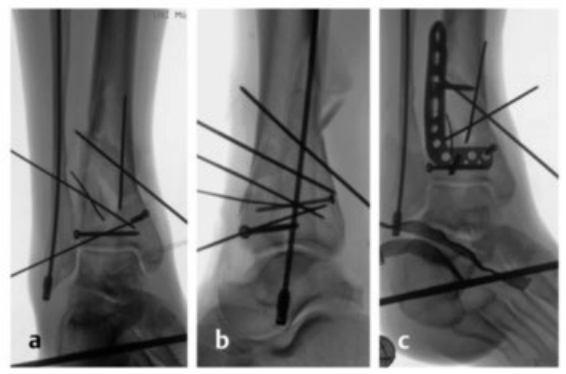

病例2受伤后入院首先植入跨踝关节外固定架,待软组织肿胀消退后,先对腓骨骨折进行微创固定,随后逐步完成复杂的胫骨Pilon骨折复位与固定。

术中临床图像显示了损伤的严重程度,同时体现了微创手术技术的优势,以及在必要时下胫腓联合切开复位重建的重要性。借助斯氏针的 “操纵杆(Joy-Stick)” 技术,可显著简化关节面的复位操作。

术后影像学随访检查显示骨折解剖复位,内植物位置良好。

患者术后恢复顺利,关节功能良好。术后12个月取出内植物,未发现创伤后关节炎征象。